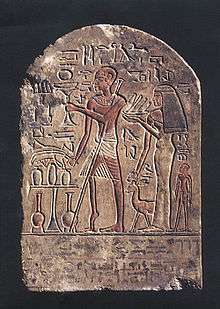

History

The effects of polio have been known since prehistory; Egyptian paintings and carvings depict otherwise healthy people with withered limbs, and children walking with canes at a young age.[124] The first clinical description was provided by the English physician Michael Underwood in 1789, where he refers to polio as "a debility of the lower extremities".[125] The work of physicians Jakob Heine in 1840 and Karl Oskar Medin in 1890 led to it being known as Heine–Medin disease.[126] The disease was later called infantile paralysis, based on its propensity to affect children.